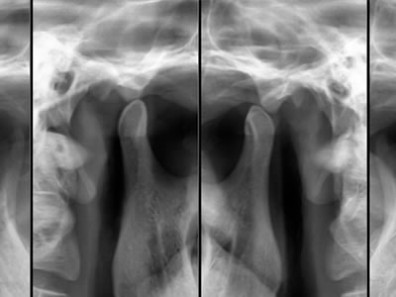

Radiografia de A.T.M.

Radiografia executada com o intuito de analisar o posicionamento da cabeça da mandíbula em relação à fossa e eminência articular em posições de boca aberta e boca fechada.